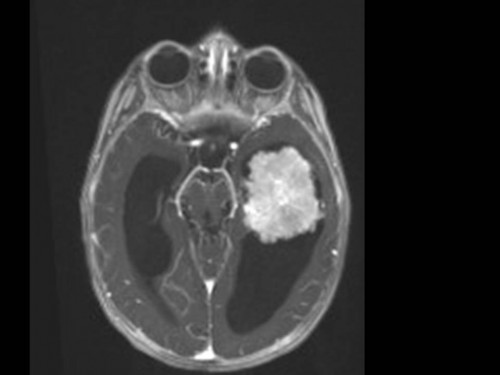

10 Monate altes Mädchen. Der Kinderarzt stellt fest, dass das kleine Mädchen einen recht großen Kopfumfang hat, nicht mit den Augen fixiert und anscheinend auch nicht richtig sehen kann. Damit bestätigt er die größten Befürchtungen der Eltern, denen in den letzten Wochen aufgefallen war, dass ihre Tochter nach keinem Spielzeug mehr greift und sie nur dann anlächelt, wenn sie zu ihr sprechen.

Bildgebung - MRT